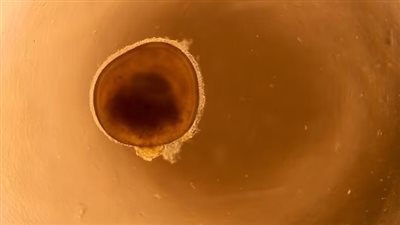

بعد شهر من الفحوصات والشكوك حول إصابته، شخّص الأطباء إصابته بعدوى بكتيرية آكلة للحم، تعرف باسم التهاب القرنية الشوكميبة، والتي يمكن أن تسبب فقدانًا دائمًا وكبيرًا للبصر، كما أصيب بحساسية للضوء أيضًا، مما يعني أنه من المؤلم أن يتعرض لآشعة الشمس المباشرة.

لم يعد بإمكان الشاب مايكل الآن الرؤية من عينه اليسرى، باستثناء الألوان الوامضة مثل السوداء والرمادية، والتي يقارنها على شاشة التليفزيون، ويقول الأطباء إنه يمكن أن يكون قادرًا على استعادة 10% فقط من الرؤية بعد عملية زرع القرنية.